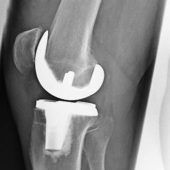

München – Im Vergleich zu vielen anderen Eingriffen ist die Erfolgsquote beim Gelenkersatz eindrucksvoll: Weit über 80 Prozent der Patienten sind mit ihrer Endoprothese zufrieden. So nennt man die Ersatzteile aus Metall, Kunststoff... zum Artikel

Einen guten Operateur zu erkennen, ist nicht ganz einfach – mit gezielten Fragen lässt sich das Risiko zumindest eingrenzen München – Manchmal lässt sich eine Gelenkersatz-Operation nicht vermeiden. Aber wenn schon, dann sollte es ein Operateur sein,... zum Artikel

Jede zehnte Operation bei einer Kniearthrose könnte laut einer DAK-Studie vermieden und ein künstliches Gelenk um mehrere Jahre hinausgezögert werden. Es gebe einen „Mangel an konservativen, nicht-medikamentösen Therapieoptionen“, stellt der jüngste... zum Artikel